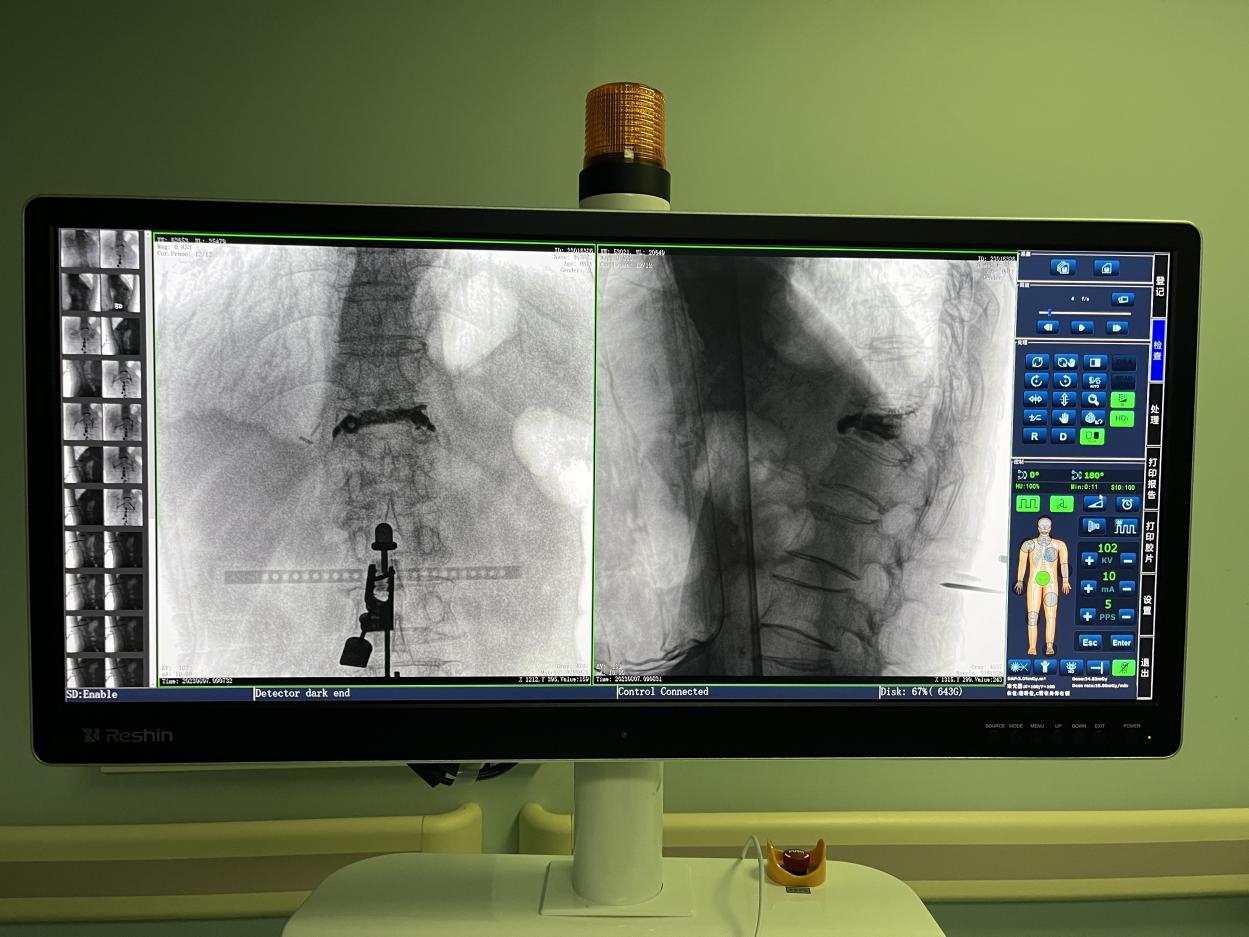

PL300B搭配普愛醫療自主研發生產的平板三維C形臂使用,通過三維立體術中圖像,手術醫生可從各個方位觀察合適的手術入路,并進行關鍵數據測量,從而最大限度地避開危險區。

骨科機器人手術-術中影像